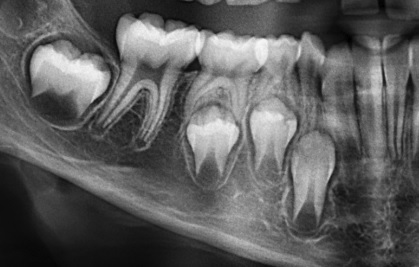

Se muestra la radiografía panorámica de una paciente femenina de 15 años de edad, en la que se observa la presencia de un defecto de RIPE de forma triangular bajo el esmalte de la cúspide distal de la pieza 38, de localización central y profundidad dentinal grado I (figura 6). En la THC adquirida, con un tamaño de vóxel de 0,2 mm, se observó un defecto dentinal de forma triangular y de grado I de profundidad, localizado en la cúspide distobucal, además de un defecto hipodenso del esmalte adyacente al defecto (figura 7).

Se tiene la radiografía panorámica de una paciente femenina de 45 años de edad, en la que se observa un defecto de RIPE en la pieza impactada 48, de localización mesial y profundidad dentinal de grado I, y, además, un segundo defecto ubicado en el centro de la corona y de forma alargada, que sería consistente con una fosa vestibular (figura 8). En la THC adquirida, con un tamaño de vóxel de 0,2 mm, se observó que el aparente defecto de RIPE mesial era, en realidad, la fosa mesiobucal y, además, se encontró un defecto de RIPE, grado I, en la cúspide distolingual asociada a un defecto hipodenso del esmalte adyacente al defecto (figuras 9, 10 y 11).